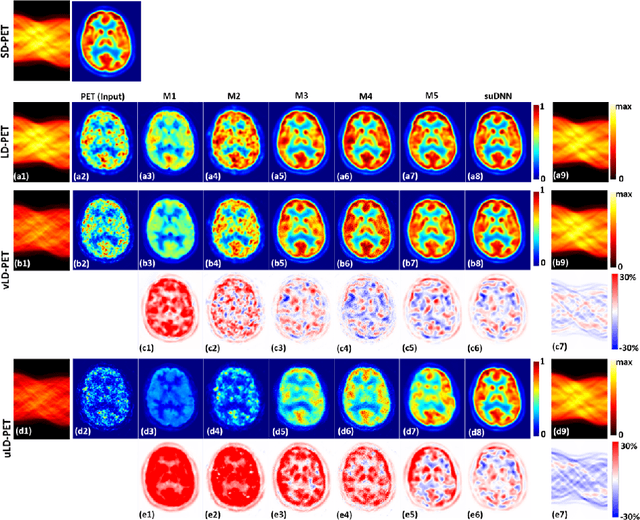

Abstract:Radiation exposure in positron emission tomography (PET) imaging limits its usage in the studies of radiation-sensitive populations, e.g., pregnant women, children, and adults that require longitudinal imaging. Reducing the PET radiotracer dose or acquisition time reduces photon counts, which can deteriorate image quality. Recent deep-neural-network (DNN) based methods for image-to-image translation enable the mapping of low-quality PET images (acquired using substantially reduced dose), coupled with the associated magnetic resonance imaging (MRI) images, to high-quality PET images. However, such DNN methods focus on applications involving test data that match the statistical characteristics of the training data very closely and give little attention to evaluating the performance of these DNNs on new out-of-distribution (OOD) acquisitions. We propose a novel DNN formulation that models the (i) underlying sinogram-based physics of the PET imaging system and (ii) the uncertainty in the DNN output through the per-voxel heteroscedasticity of the residuals between the predicted and the high-quality reference images. Our sinogram-based uncertainty-aware DNN framework, namely, suDNN, estimates a standard-dose PET image using multimodal input in the form of (i) a low-dose/low-count PET image and (ii) the corresponding multi-contrast MRI images, leading to improved robustness of suDNN to OOD acquisitions. Results on in vivo simultaneous PET-MRI, and various forms of OOD data in PET-MRI, show the benefits of suDNN over the current state of the art, quantitatively and qualitatively.